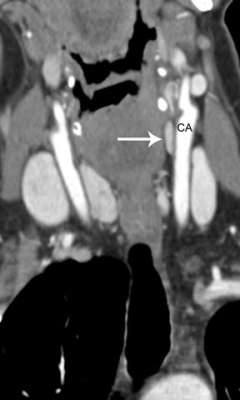

Re-do Parathyroid Surgery

Common locations of missed parathyroid adenomas.